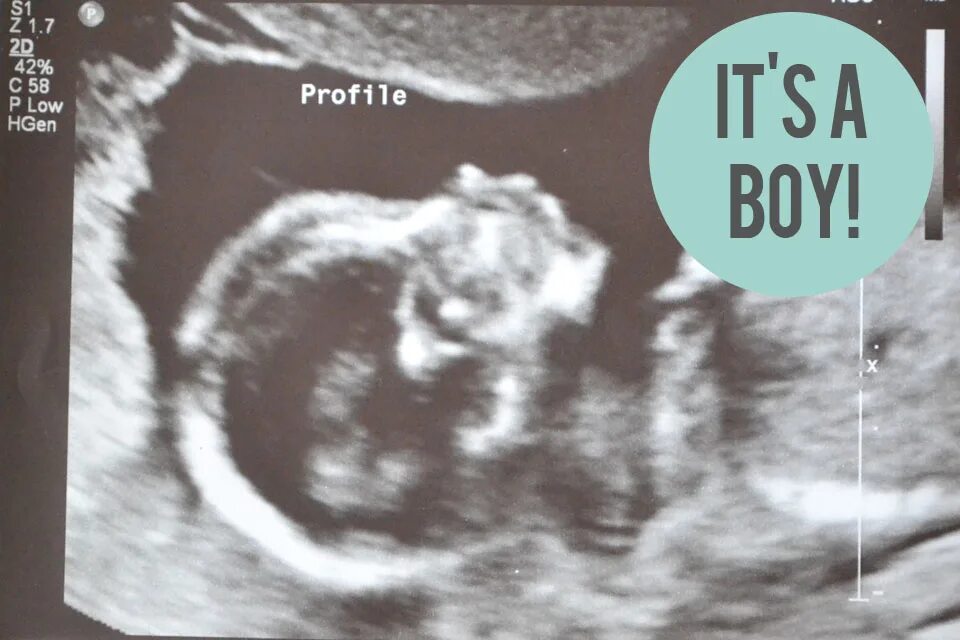

Ребенок в 13 недель